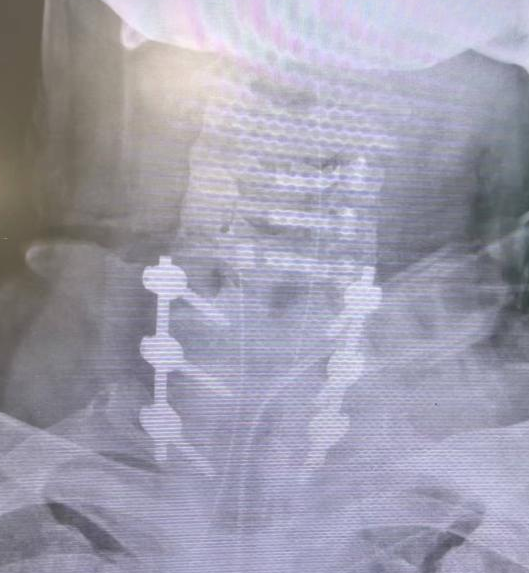

经过充分术前准备,张鹏主任医师手术团队按计划行颈后路手术。全麻后,团队谨慎完成患者体位摆放,术中见硬脊膜撕裂、颈髓损伤伴脑脊液外溢。手术团队实施彻底清创,完成椎弓根内固定以稳定骨折,并结合单开门与双开门术式实现椎管充分减压,最后置管引流。手术历时三小时,过程顺利,患者转危为安。